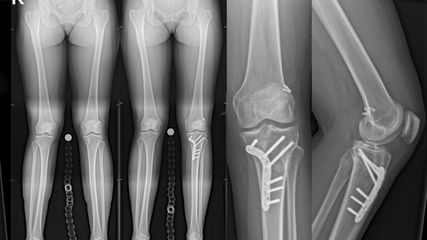

Bisher galt die SAD als unheilbar. Die Methode des transversalen Tibiatransportes (TTT) könnte erstmals eine Option für diese Patienten darstellen (siehe hierzu den Artikel „Transversaler Tibiatransport: Option bei DFS mit schwerer ,small arterial disease‘?“).

Angeborene Fehlstellungen des Unterschenkels

Kongenitale Deformitäten des Unterschenkels gehören zu den seltenen, aber medizinisch bedeutenden und operativ herausfordernden Diagnosen der Kinderorthopädie. Eine differenzierte ...